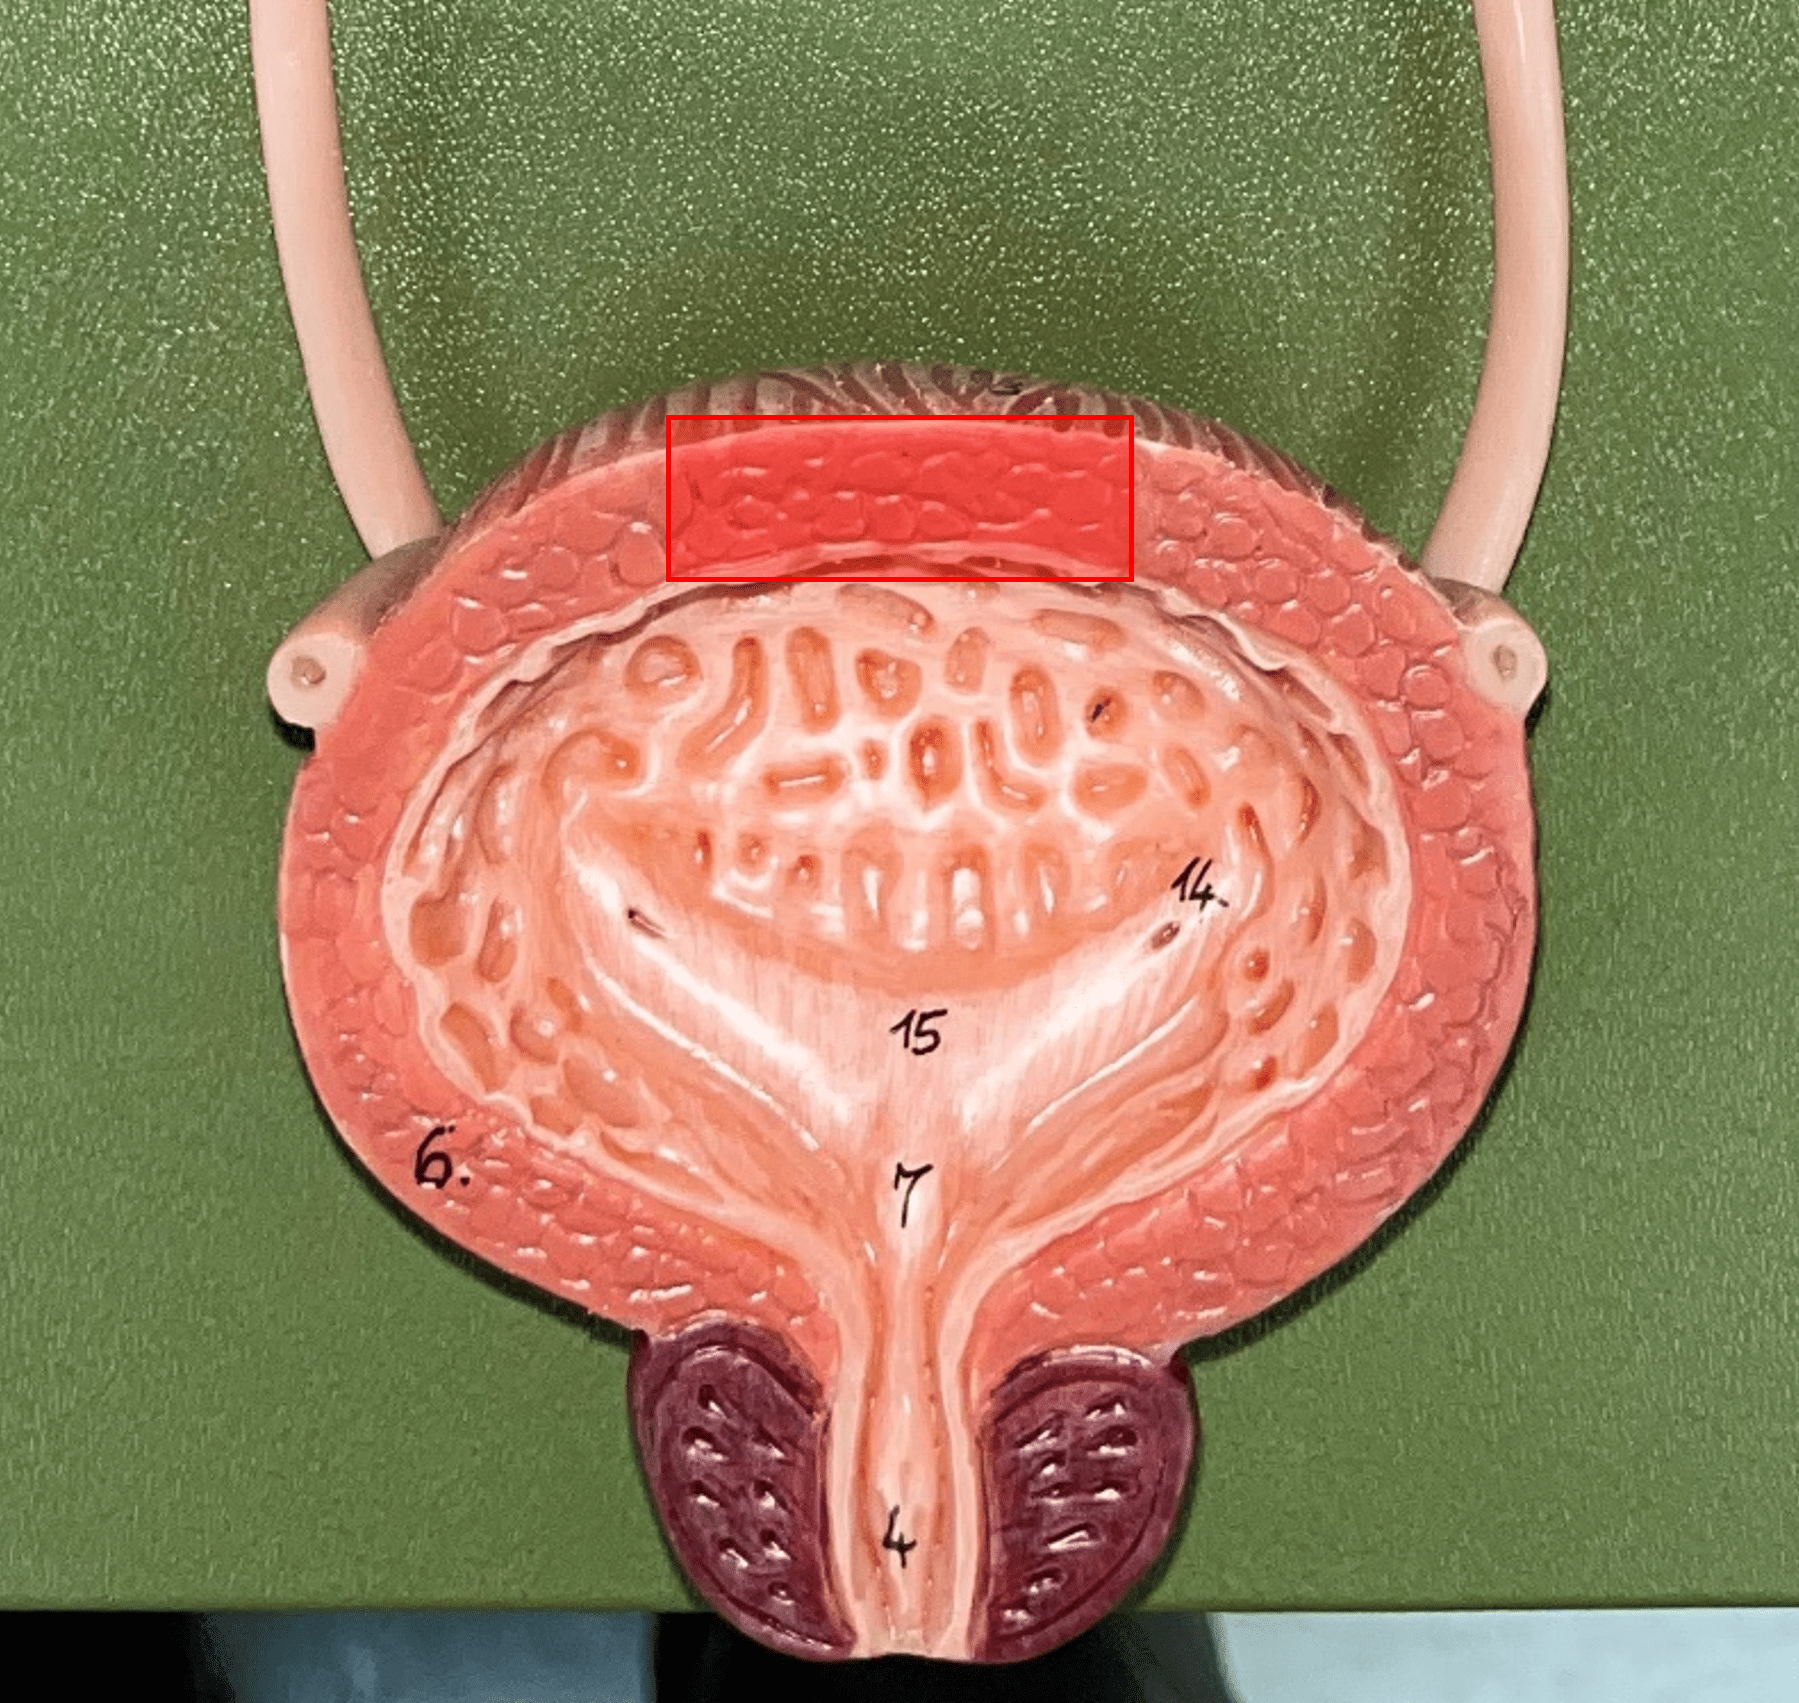

detrusor muscle

• Part of the urinary bladder.

• The muscularis of the bladder.

• Contracts to expel urine from the bladder.

• The muscularis of the bladder.

• Contracts to expel urine from the bladder.